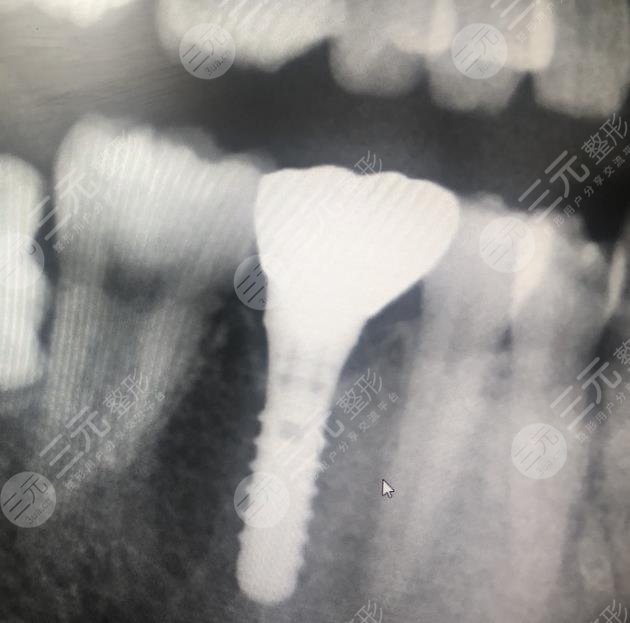

I am a lecturer in the company, usually I may have to face the whole company for training, so the requirements for appearance are relatively high, because not long ago I lost a tooth, resulting in the whole appearance has also been affected, and when I speak, it is also very uncomfortable, so I have always wanted to carry out dental restoration, and later under the introduction of a friend, I found a local well-known dental hospital, in fact, when I was looking for a hospital, I also learned some related methods of repairing teeth, in fact, I am more inclined to dental implants After coming to the hospital, I didn't expect the doctor to recommend dental implant surgery to me.

The price of dental implants may be relatively high, but I know that the results are better, and the maintenance time will be longer, it can be said that it can bring a one-time treatment, before doing dental treatment, the doctor also introduced me to some related knowledge, I know a lot, during the operation injected anesthetic, so I will not feel pain at all, this is not to worry. When I just had dental implant surgery, I may feel some swelling, and there will also be bleeding, I was like this at the time, and the doctor who was still worried at that time told me some relevant details for me to pay special attention to, this situation is normal, generally it will slowly disappear in about 3 to 5 days, and if it is really on the 4th day, my tooth swelling will slowly disappear.

It has been more than two months since I had dental implant surgery, because the time period of dental implant surgery is very long, but according to the good results, the whole tooth is better, and I can chew food normally, just like my own real teeth, I am more grateful to the doctor for the help I have brought to me, of course, I am also glad that I chose this hospital, I have many friends with bad teeth around me I also recommended them to come to this hospital for treatment, I believe that I will be able to get better dental restoration.